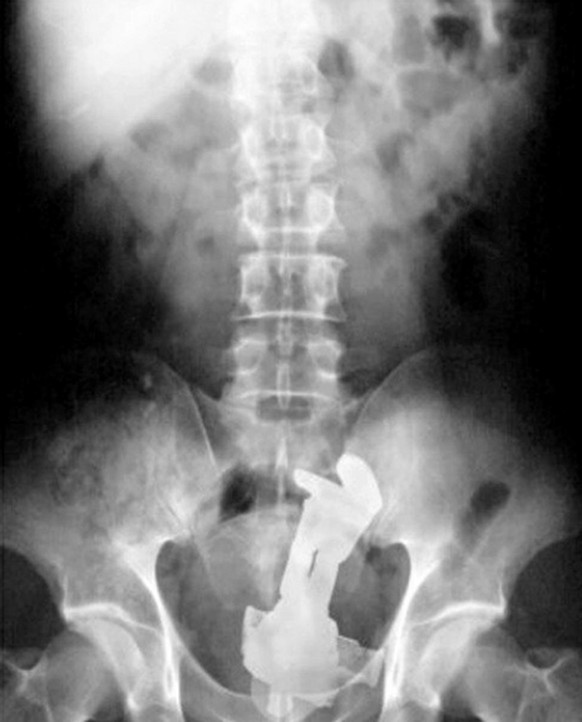

Imaginez la conversation inconfortable avec le personnel médical...